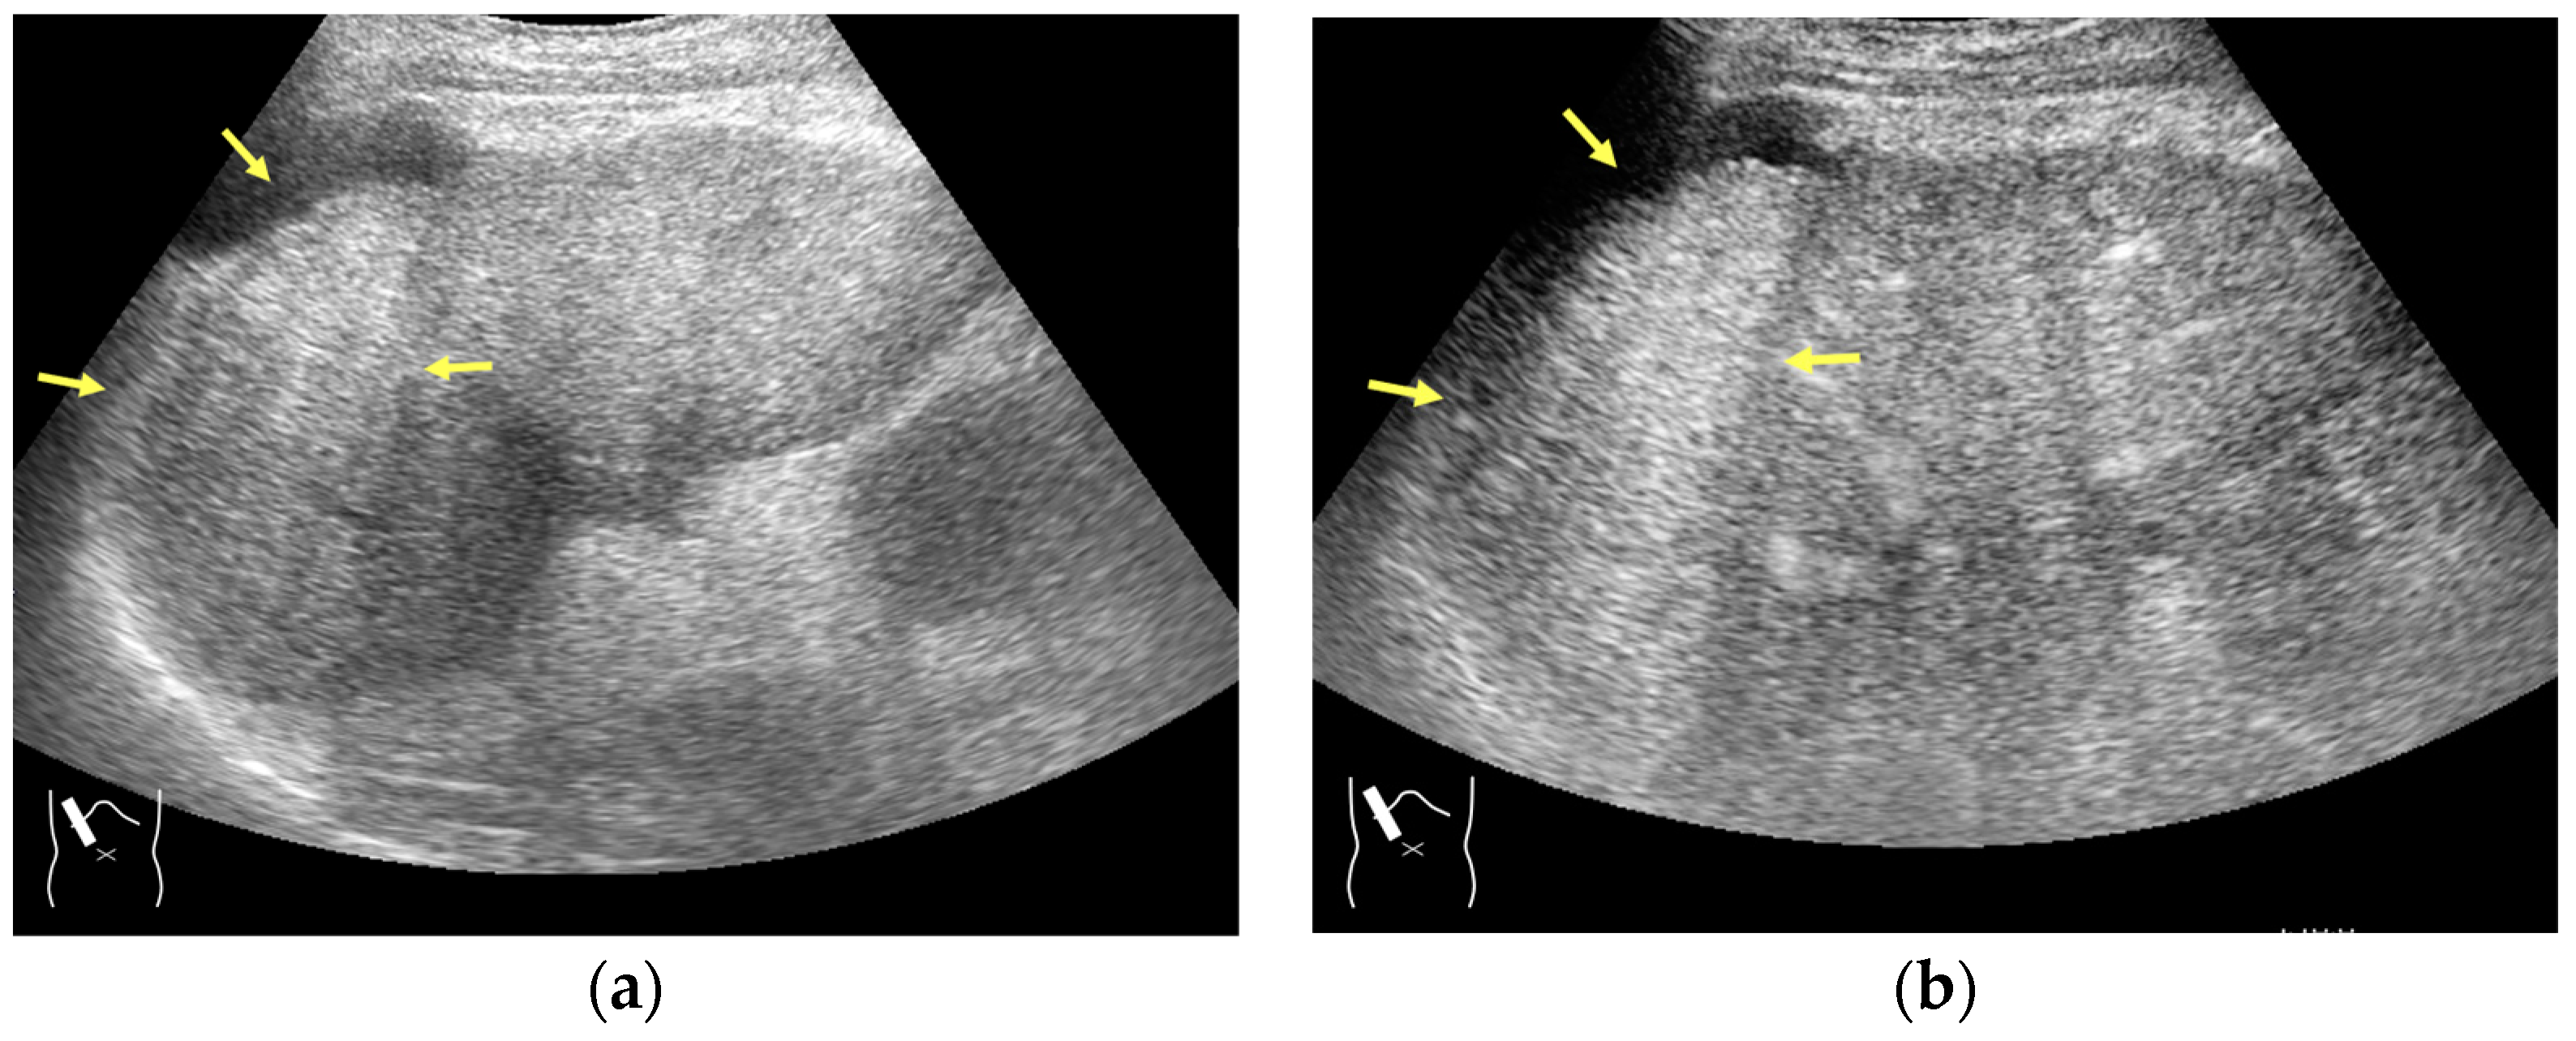

The image frame rate (the number of times/second) is a characteristic of US examinations, and it is closely related to the temporal resolution. The higher the frame rate, the faster the image movement [30,31], which allows for rapid survey scans of the target lesion [32]. Meanwhile, the number of US beam lines is generally related to the spatial resolution. The smaller the number of US beams, the faster the scanning speed. However, this can compromise the US image quality (Figure 1a,b). Thus, it is important to balance the frame rate and the image quality in US examinations. Another way to increase the frame rate is to reduce the image width, i.e., narrowing the view angle. This method can be easily performed even with middle-price CEUS machines (Figure 1c). Thus, there are two ways to gain high-frame rate CEUS images using current CEUS machines: (a) narrowing the frame angle (as shown in Figure 1c) and (b) decreasing the number of US beams. The former keeps the same spatial resolution and is suitable for observing small lesions. The latter is only available with high-end CEUS machines and is suitable for observing relatively large lesions.

Figure 1.

A schematic drawing of high-frame-rate CEUS: (a) narrowing the viewing angle; (b) decreasing the number of ultrasound beams; (c) representative CEUS image of the method (a,c): frame rate 12/s; (d): frame rate 30/s (focal nodular hyperplasia, arrows). A more detailed vascular structure (in this case, it has a spoke-wheel appearance) can be displayed using high-frame-rate CEUS when observing hypervascular mass lesions.

The current high-end machines have the above two functions. By selecting function (b), the machine automatically decreases the number of US beams (usually to half of the usual number) and increases the frame rate (usually to twice the usual rate) without changing the width of the field of view. This function is especially useful when observing the vascular structures of high-flow liver tumors.